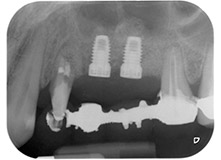

58-годишна пациентка се оплаква от болка и повишена подвижност в нейния мост върху зъб 24 с функция на абатмънт. На лице е периодонтално възпаление с дълбочина на джоба 7 mm мезиобукално и повече от 12 mm дистално, както и включена 3 градусова фуркация. Освен това, рентгенографията показва обширна периодонтална лезия около апикалната зона на (друго място) предварително ендодонтски обработен зъб 24 (Фиг. 1).

В букалния корен, цялата вестибуларна и дистална кост липсва. Захващането е значително ограничено до палатиналния корен, подчертавайки предварително лошата прогноза. Зъб 27 също откри намалено хоризонтално захващане и минимално апикално разреждане (Фиг. 1) без клинични симптоми.